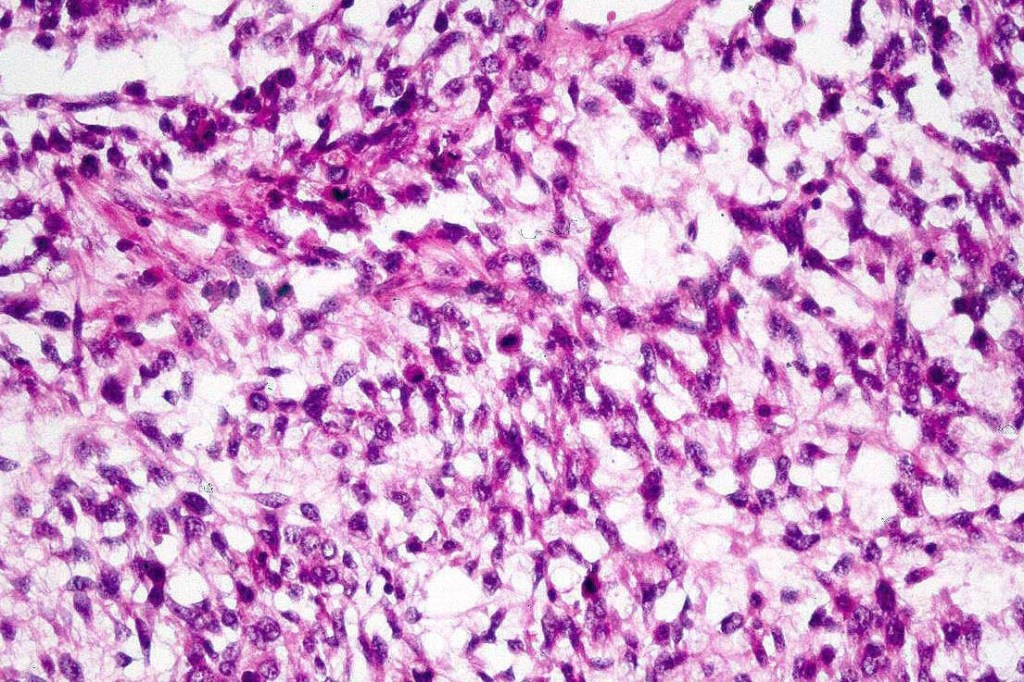

A rare variant of melanoma in which stromal cells produce excess acid mucopolysaccharides inprting a striking myxoid quality. The mucin is Alcian blue & colloidal iron positive, DPAS negative and the melanoma cells stain with typical markeres including S100 & HMB45. It may be seen in primary, recurrent or most often in metastatic lesions. The tumor cells are typically small although occcasionally they are epithelioid. Melanin is often sparse or even avsent making diagnosis difficult. In some examples, a pseudoglandular appearance is seen.

The differential diagnosis is very wide and can include numerous myxoid soft tissue tumors and epthelial mucin-secreting carcinomas. Diagnosis depends on clinical history, mucin stains and the judicious use of immunohistochemistry.